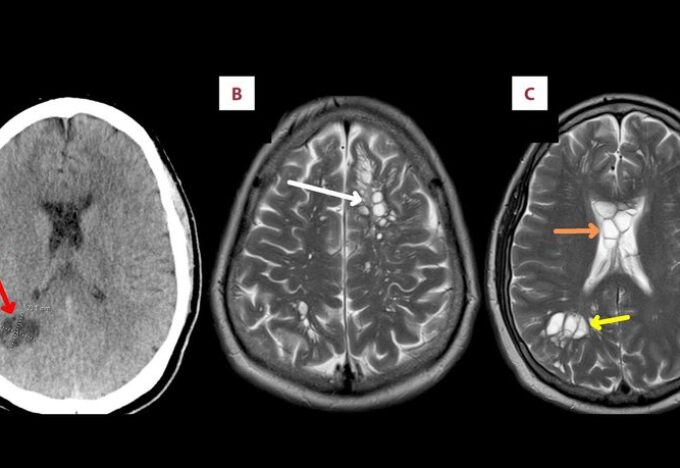

اكتشاف بيوض الدودة الشريطية في دماغ رجل بسبب اللحم المقدد

اكتشف رجل أمريكي في الخمسينات من العمر وجود بيض الدودة الشريطية في دماغه بعد زيادة آلام الصداع النصفي التي كان…